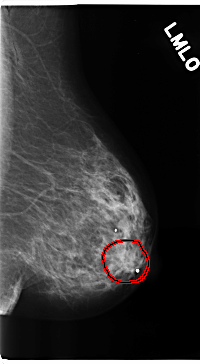

FILE: C_0206_1.LEFT_MLO.OVERLAY

TOTAL_ABNORMALITIES 1

ABNORMALITY 1

LESION_TYPE MASS SHAPE LOBULATED MARGINS ILL_DEFINED

ASSESSMENT 4

SUBTLETY 3

PATHOLOGY MALIGNANT

TOTAL_OUTLINES 1

BOUNDARY

LEFT_MLO LINES 4728 PIXELS_PER_LINE 2592 BITS_PER_PIXEL 12 RESOLUTION 50 OVERLAY